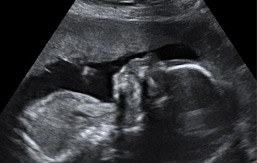

Ecografías de la semana 27 de embarazo

Ecografía semana 27: cabeza de perfil. Vemos perfectamente en esta imagen ecográfica la órbita ocular del bebé, la nariz y la boca. Se visualizan tanto faringe como huesos maxilares.